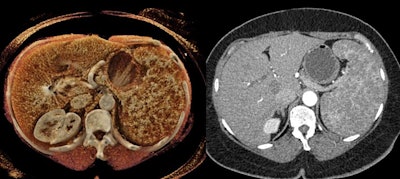

Cinematic rendering allowed radiologists from Johns Hopkins University to uncover key features of spleen anatomy and pathology not evident on conventional CT scans -- carving out yet another niche role for the technique, which they detailed in an article recently published online in Diagnostic and Interventional Imaging.

At their institution, Dr. Elliot Fishman; Dr. Steven Rowe, PhD; and colleagues have explored the possible advantages of incorporating cinematic rendering -- a 3D visualization technique characterized by highly photorealistic detail and shadowing -- into the evaluation of aortic complications and gastric and renal pathologies, among numerous other clinical applications.

- Vascular conditions: Cinematic rendering is particularly well suited for visualizing vasculature near the hilum of the spleen, an area frequently affected by stomach and pancreatic tumors that restrict blood flow to certain parts of the spleen. Cinematically rendered CT scans display clear demarcations between these infarcted regions and otherwise stable areas.

In addition, the advanced visualization technique clearly depicts textural changes and fluid leakage in the spleen commonly associated with lacerations in trauma patients. These findings may additionally be able to help predict a patient's need for splenectomy.